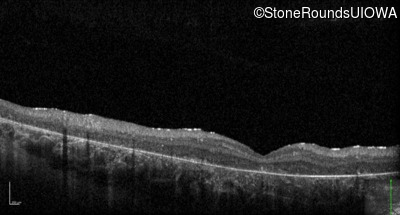

Optical Coherence Tomography - Left - 10/400 sc

Exemplar / OCT Stack